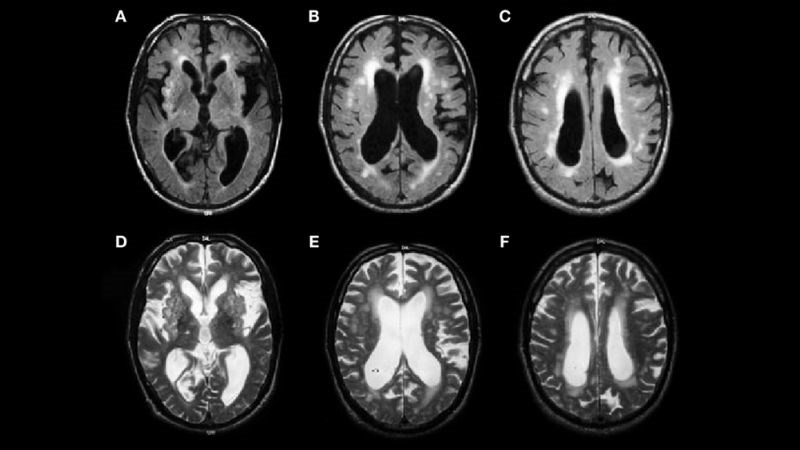

- Chẩn đoán hình ảnh: CT hoặc MRI sọ não để kiểm tra các bất thường ở não.[3]

Chụp MRI giúp khảo sát các nguyên nhân gây run tay chân ở não